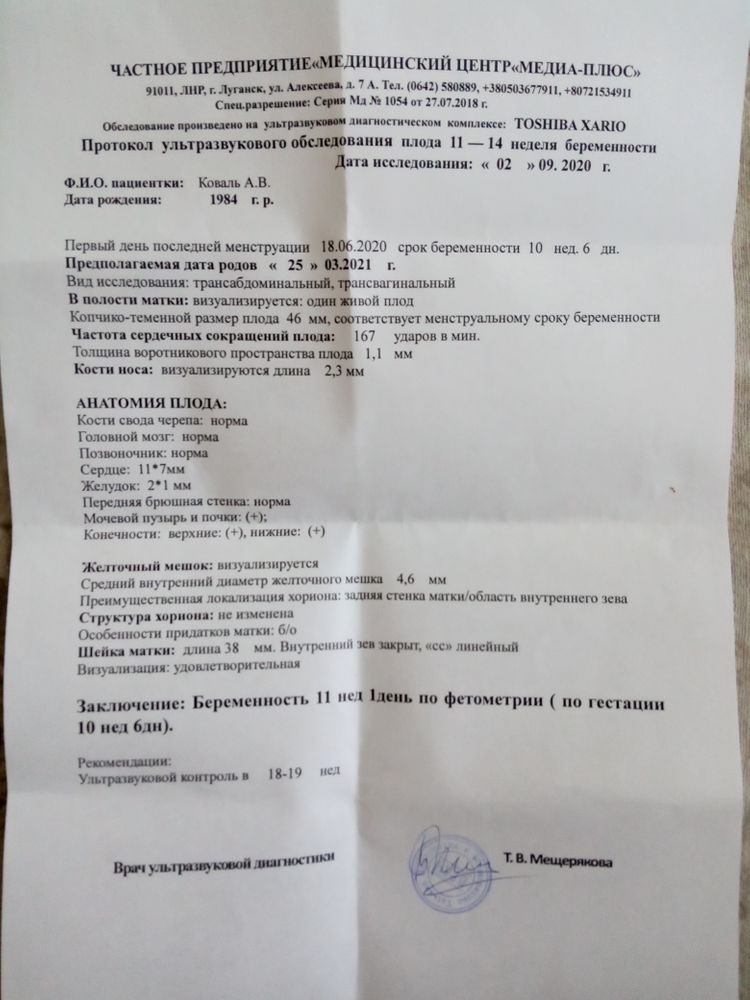

Вчера делали первый скрининг, а точнее Узи, кровь сдала сегодня. По УЗИ у нас всё отлично, результаты крови будут завтра. Но я уверена,что всё у нас отлично. На УЗИ со мной ходили муж и старшая дочь, видели как малыш машет ручками и ножками, это так трогательно! И дали нам фотку первую)